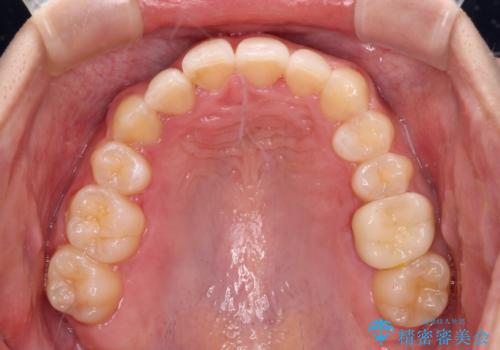

- 上顎の重なっている前歯を気にして来院された患者様です。

八重歯改善には抜歯が必要で、八重歯の移動量が多く、更には右側にずれている正中を改善する必要がありました。

インビザライン単体での治療は困難と判断し、補助装置により八重歯移動後にインビザラインを用いることとしました。